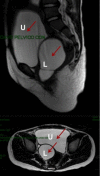

Herlyn-Werner-Wunderlich syndrome (HWWS) is a rare congenital mullerian anomaly consisting of uterus didelphys, hemivaginal septum, and unilateral renal agenesis [1,2]. Most authors reported cases of Herlyn-Werner-Wunderlich syndrome with prepuberal or postpuberal onset with cyclical abdominal pain and a vaginal mass (3-8). Only six cases are reported in Literature with early onset of this syndrome under 5 years (9-14). Our case is about 3 years old girl, with all the features of this syndrome who came to our attention for lower abdominal mass. The aim of this article is to share our experience and focus the attention on the importance of high level of suspicion of HWWS in neonatal period to early diagnosis and treatment. The possible early presentation of this syndrome should be suspected in all neonates (females) with renal agenesia confirmed postnatally or with prenatal diagnosis. It is common, in fact, an error of evaluation with planning of removal of mass, that can damage patients in term of chance for a successful reproductive outcome. For all these reasons, our team consider HWWS as differential diagnosis in newborn with prenatal ultrasonography of a cystic mass behind the urinary bladder in the absence of a kidney and plan a pelvic ultrasound (with aim to identify an uterus, normal or dydhelfus, and presence or absence of pelvic mass), an examination under anesthesia and cystoscopy and vaginoscopy, if it is necessary. A high level of suspicion, indeed, is the key to early diagnosis.